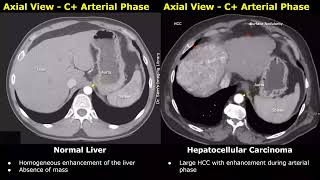

CT Scan Liver Normal Vs Hepatocellular Carcinoma (HCC) Images | Liver Cancer Imaging Diagnoses